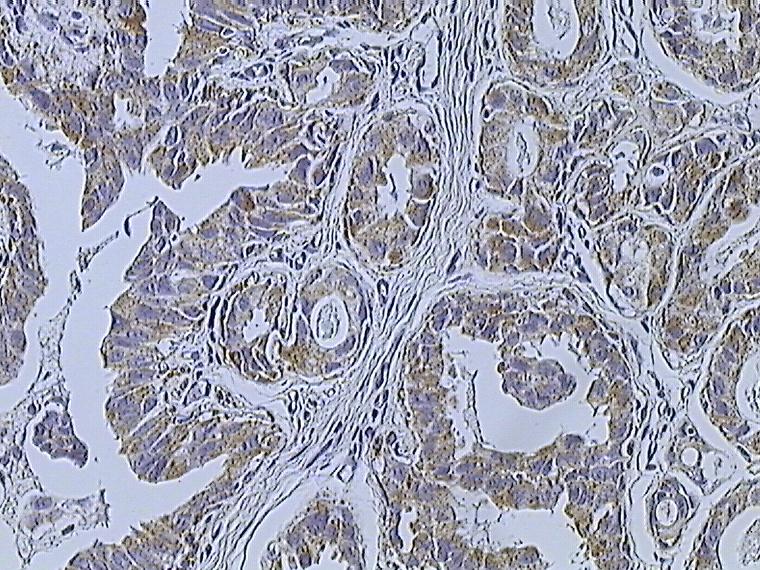

- Estrogen receptor (ER) status

- Progesterone receptor (PR) status

Both estrogen receptor (ER) and progesterone receptor (PR) are found in the nucleus, and their existence is linked to a response to anti-estrogenic drugs like tamoxifen.